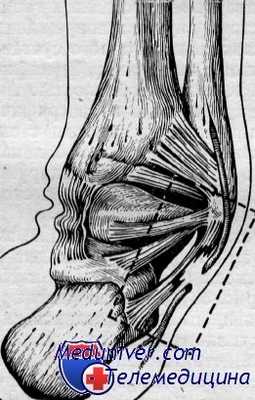

Добавочная треугольная кость таранной кости является вариантом развития и располагается в заднем отделе таранной кости. Задний отросток таранной кости имеет свое ядро окостенения. Возможно, что в годы обучения в хореографическом училище и раннего начала нефизиологических движений (положение стопы на. пуантах) ядро окостенения заднего отростка не сливается с основной костью и остается в виде добавочной треугольной кости.

У артистов балета она встречается часто, почти в 7з случаев. Клинически она ничем себя не проявляет, если нет большой нагрузки.

У артистов балета классического танца при выполнении прыжковых партий, при положении стопы па пуантах эта кость может вызвать болезненные явления. Появляются боли, чувство заклинивания в суставе и развиваются явления деформирующего артроза между таранной костью и треугольной добавочной костью.

При осмотре видимой патологии не обнаруживается, только при глубокой пальпации определяется болезненное подвижное тело. Диагноз уточняется исключительно рентгенологически, когда определяется треугольной формы тело в заднем отделе таранной кости с ровными контурами.

Лечение в начальной стадии можно начать с консервативного (инъекции новокаина с введением гидрокортизона). Быстро ликвидируются боли и восстанавливается трудоспособность. Но наличие частых блокад, обострений болевого синдрома и нарушения трудоспособности являются абсолютными показаниями к оперативному удалению этой кости.

В других случаях может быть обнаружен увеличенный задний отросток таранной кости, который вызывает боль при соприкосновении с задним отделом большеберцовой кости. В этих случаях также производят оперативное удаление увеличенного отростка таранной кости.